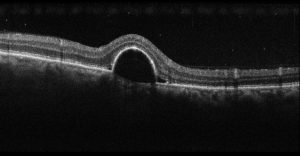

La tomografia a coerenza ottica (OCT) è un test di imaging non invasivo che utilizza le onde di luce per scattare foto della retina, e in particolare della macula. La macula è una parte della retina deputata alla visione a colori e ad alta definizione.

Con l’OCT possono essere analizzati e mappati tutti gli strati retinici, inoltre è possibile rilevare lo spessore retinico. Questi dati aiutano a effettuare una corretta diagnosi e a fornire delle indicazioni per il trattamento del glaucoma e delle patologie retiniche, malattie come la degenerazione maculare senile e la retinopatia diabetica.

Se in atto è presente o è stata presente una di queste condizioni retiniche è importante eseguire l’OCT.